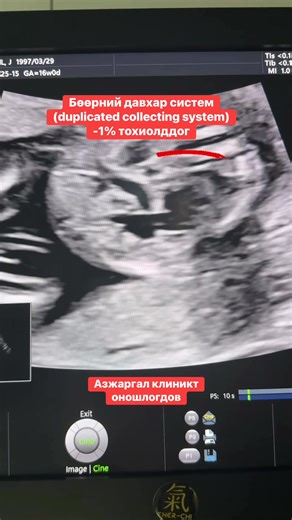

Ureter - Duplicate Collecting

System Kidneys - Duplex Right